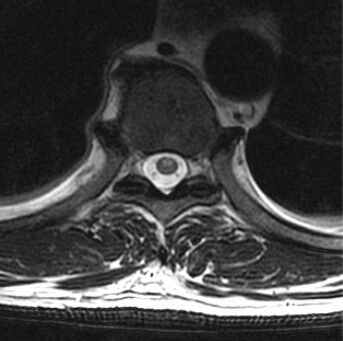

72.51歲男性主訴跌倒後數小時開始出現四肢無力且大小便失禁,圖為病人的胸椎磁振造影影像 (T2WI),下列敘述何者錯誤?(A)臨床表現和影像符合spinal cord infarction(B)spinal cord infarction在磁振造影中,脊髓可能見到owl's eye表現(C)受影響的血管最常是posterior spinal artery(D)脊髓的主要血液供應來自一條anterior spinal artery和一對posterior spinal arteries